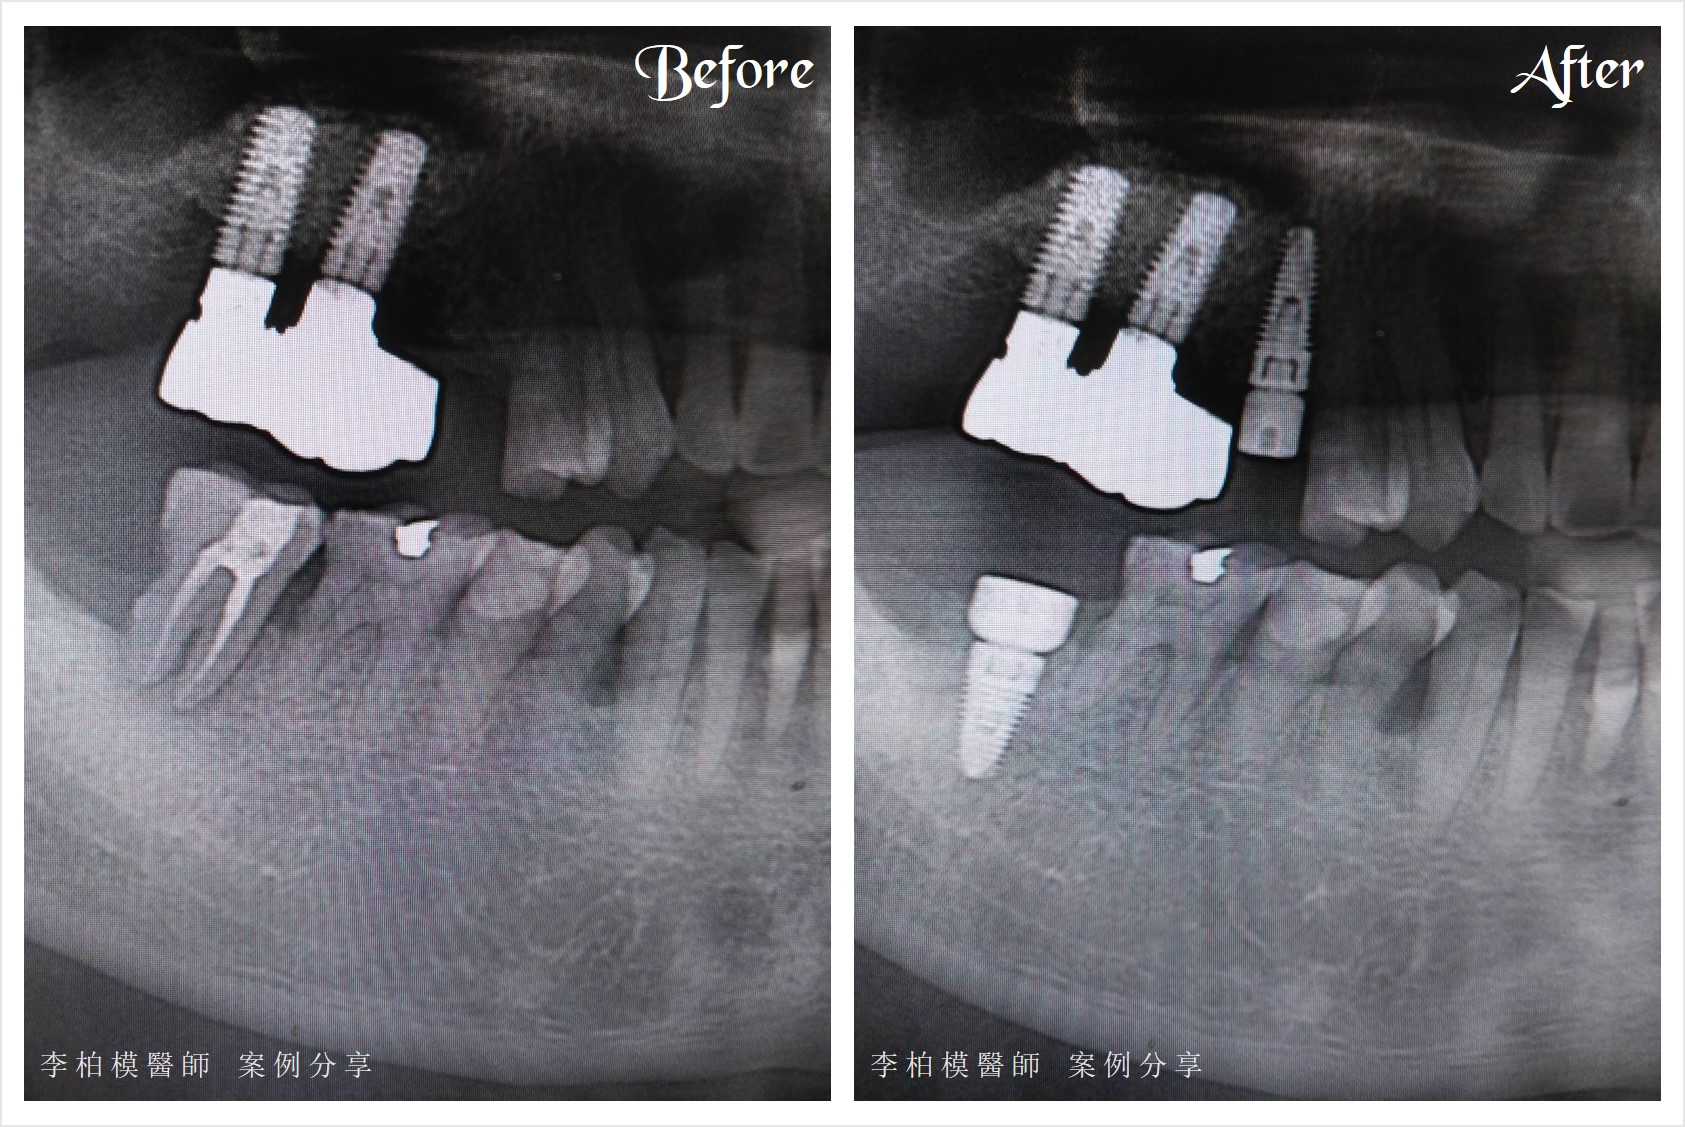

▲#2

李醫師為患者進行即拔即植手術,和完成四合一(拔牙、植牙、補骨、接合),

全程無針無縫無膜,整個過程中只放了4樣東西:麻藥、植體、Biooss骨粉,和最後敷料的複合樹脂。

患者手術結束後驚訝地說:「現在的醫學真的很進步。」

因為操作中沒有使用多餘的外來物,也沒有太長時間或大範圍的手術,

2天後電話慰問,患者說狀況一切正常,恢復良好。